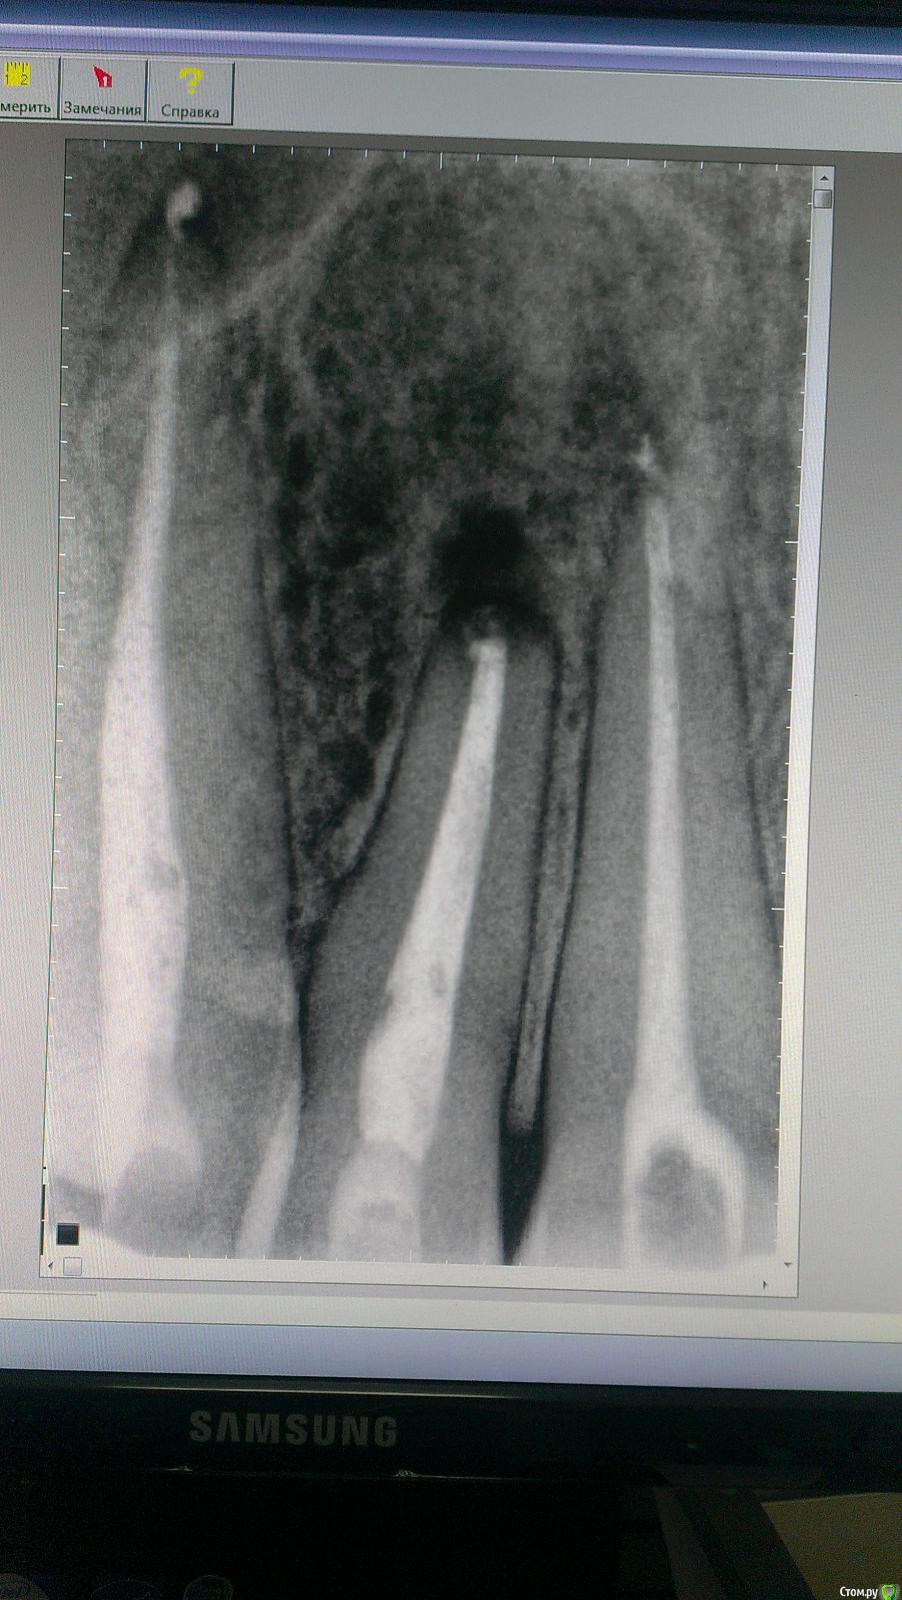

vesta Опубликовано 4 января, 2015 Поделиться Опубликовано 4 января, 2015 Пациент обратился с жалобами на боль в 1.2. Два года назад удаляли кисту в области 1.1, 1.2 (причинный), 1.3. Сейчас перкуссия 1.2 болезненная, 1.3 - слабо болезненная. Переходная без видимых изменений, болезненная при пальпации. Что делать? Повторное хирургическое или эндолечение? Ссылка на комментарий

SDC Опубликовано 4 января, 2015 Поделиться Опубликовано 4 января, 2015 (изменено) Сначала повторное эндо всех трех, мониторинг, в случае необходимости ретроградно. Изменено 4 января, 2015 пользователем SDC Ссылка на комментарий

JIM Опубликовано 15 января, 2015 Поделиться Опубликовано 15 января, 2015 Стоит сделать КТ... ведь кортикальки там может и не быть, и решать совместно с хирургом Ссылка на комментарий